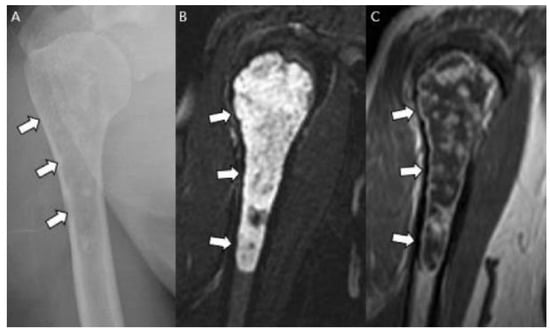

3.3. Distinction between ACT/CS1 and High-Grade Chondrosarcoma

- Littrell, L.A.; Wenger, D.E.; Wold, L.E.; Bertoni, F.; Unni, K.K.; White, L.; Kandel, R.; Sundaram, M. Radiographic, CT, and MR Imaging Features of Dedifferentiated Chondrosarcomas: A Retrospective Review of 174 De Novo Cases. Radiographics 2004, 24, 1397–1409. [Google Scholar] [CrossRef]

- MacSweeney, F.; Darby, A.; Saifuddin, A. Dedifferentiated chondrosarcoma of the appendicular skeleton: MRI-pathological correlation. Skelet. Radiol. 2003, 32, 671–678. [Google Scholar] [CrossRef]